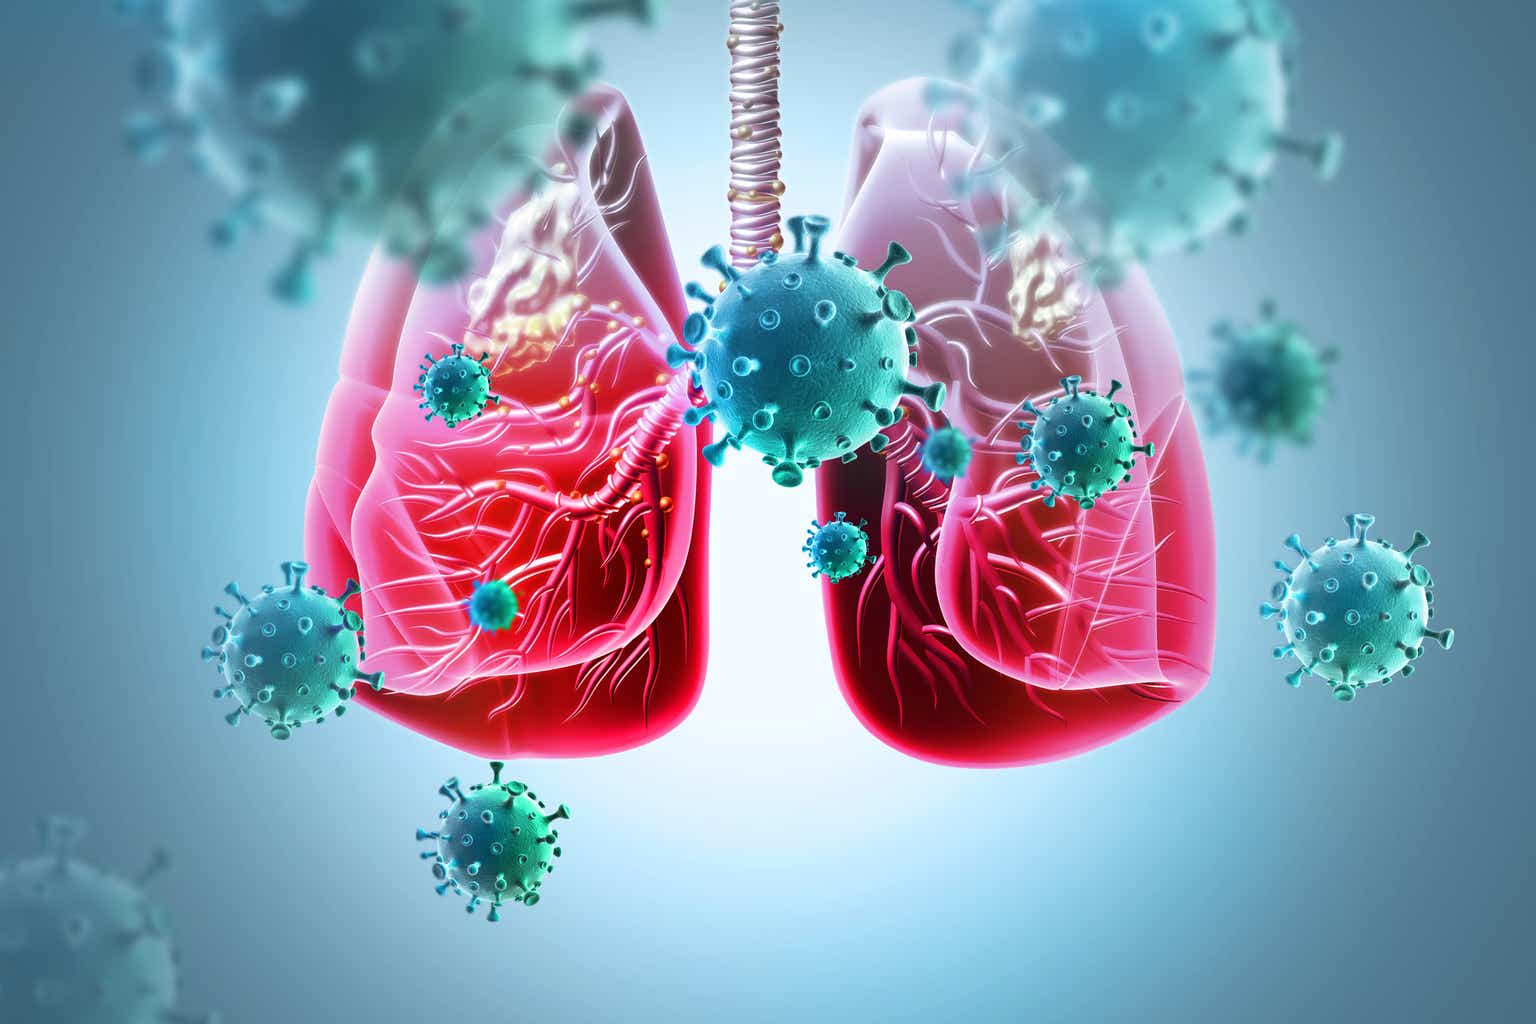

Раздел: Фотоэссе